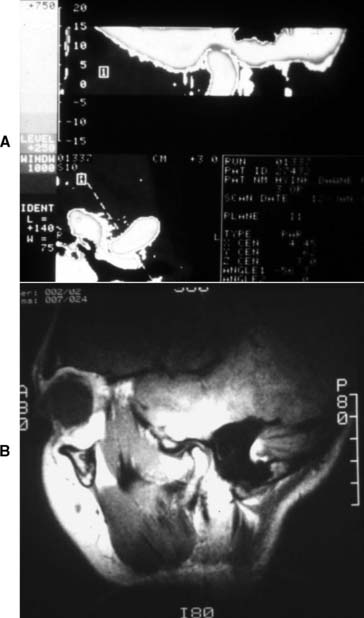

Special radiographs may be needed for the assessment of TMJ disorders and a wide variety of pathologies ranging from bone and mineral disorders to metabolic disorders, genetic abnormalities, and soft tissue calcifications such as carotid artery calcification.21 For assessment of the TMJs, a transcranial exposure (Fig. 1-25), with the help of a positioning device, reveals the lateral third of the mandibular condyle and can be used to detect structural and positional changes. However, interpretation may be difficult,22 and more information may be obtained from other images23 (Fig. 1-26).